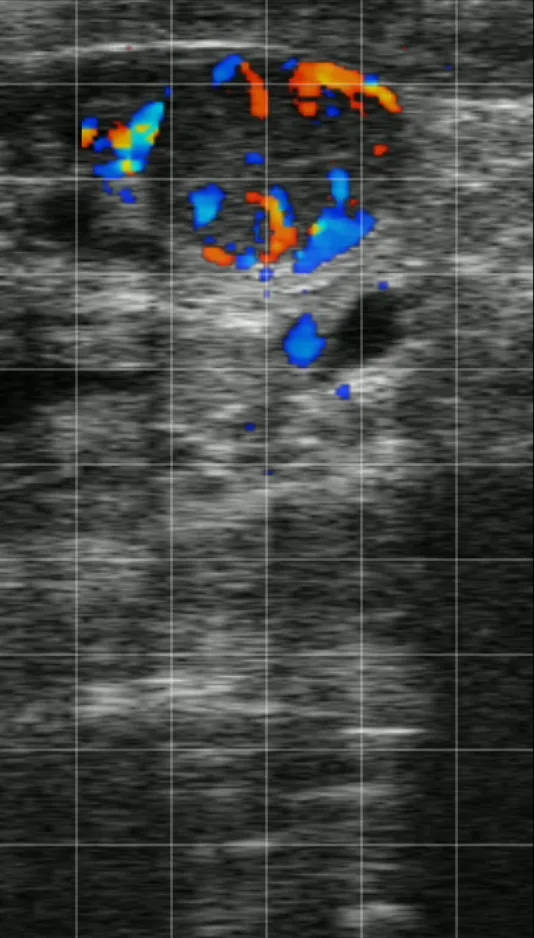

Essentially, CFM shows blood flow to and from a structure. On the Easi-Scan:Go, CFM can be used to examine the ovary and by examining blood flow you can determine a non-pregnant cow, 18 days post insemination. This aids getting cows in calf faster, increasing milk and meat output on the farm.

Corpus luteum CFM on ESG 2

With pre-set, optimised for low velocity blood flow in the CL, and B+CFM mode, this product makes a scanning process and embracing the new technology really easy. Our CFM pre-set is designed with the bovine uterus in mind. Blood in the uterus does not circulate as fast as in other areas of the body and requires different imaging techniques, settings and scanner capabilities for accuracy.

CFM